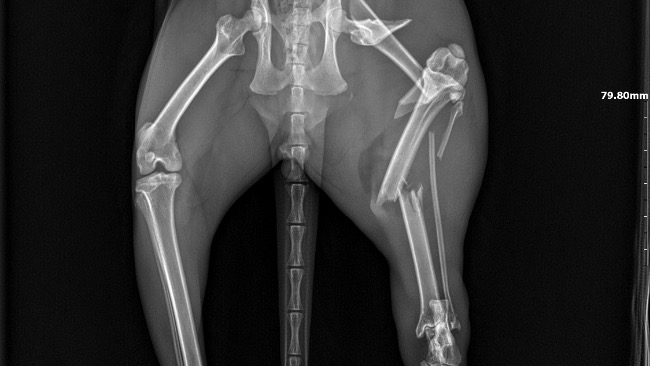

Dziś Pani Ania z Przychodnia Weterynaryjna CapraVet zrobiła zdjęcie rtg łapki. Okazało się, ze ta jest złamana w trzech miejscach 😱Takiego urazu mógł się nabawić tylko w bliskim spotkaniu z pędzącym autem 😢 Filemon niestety przebiegał 32. Tym razem nie zdążył. Na szczęście, choć poturbowany, dotarł na swoje śmieci. Gdyby skrył się gdzieś w krzakach…

Takie złamanie trzeba szybko operować.

Za radą Gosi Pietrzyk napisałam do Przychodni weterynaryjnej Sanatus w Krosinku. Pani Ania mówi, ze są najlepsi. Kazali mi przywieźć Filemona jutro, we wtorek będzie operowany. Koszt operacji to 1.200 zl. Do tego trzeba doliczyć leczenie po operacji, środki przeciwbólowe, potem usunięcie drutów. Stąd ta zbiórka.